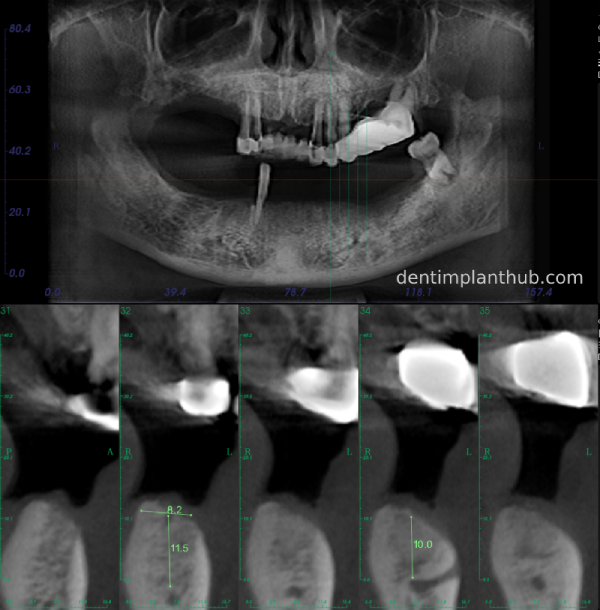

A review of the CBCT on 6/10/23 was more promising and a surgical plan was subsequently drawn up.

46

44

42

32

34

36

General schematic of the surgical programme

Detailed list of implant types and composite abutments to be prepared.

46 tooth position, implant model number 4810, RC series straight composite abutment;

44 tooth position, implant model number 4110, RC series straight composite abutment;

42 tooth position, implant model number 4110, RC series straight composite abutment; alternate implant model number 3310, alternate NC series straight composite abutment;

32 tooth position, implant model number 4110, RC series straight composite abutment; alternate implant model number 3310,. Alternate NC Series Straight Composite Abutment;

34 Dental Position, Implant Model No. 4110, RC Series Straight Composite Abutment;

36 Dental Position, Implant Model No. 4808, RC Series Straight Composite Abutment;